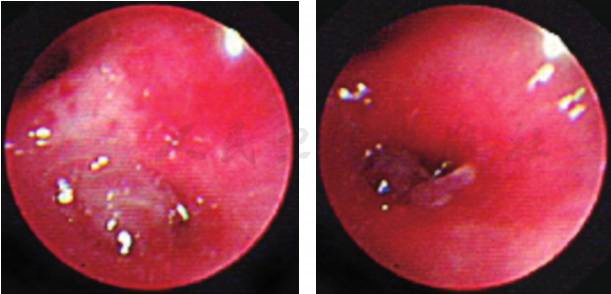

入院第二天行纤维支气管镜检查,镜下可见左肺舌叶(B4、B5)开口处可见一块肿物堵塞大部分管腔(图3),予活检钳钳取部分肿物和留取支气管灌洗液,送病理检查。病理结果回报(图4):(支气管)慢性炎症,局灶见不典型类上皮结节,不除外结核。因此考虑患儿是支气管淋巴结核,结核分枝杆菌突破相邻的支气管内膜,干酪样物进入管腔导致气管腔阻塞。因此增加了抗结核的种类,给予患儿三联抗结核药物(异烟肼、利福平、吡嗪酰胺)口服治疗1个月复查支气管镜。第二次支气管镜下舌叶(B4、B5)开口处可见(图5)黄白色干酪样物质周围被肉芽组织包裹完全堵塞其开口,先用活检钳反复钳取黄白色干酪样物质,并将钳取物分别涂片镜检并送活组织病理检查,考虑常规口服抗结核药物渗透到支气管内膜的浓度小,对局部治疗效果差,因此取了病理后对肉芽组织以及干酪样物进行4次冷冻治疗(每次冷冻时间30~60秒不等)和反复多次钳取,治疗结束后,B5支气管开口得以暴露(图6),其支气管管腔开口通畅,可见正常B5亚段结构,但B4支气管开口仍被肉芽组织覆盖(图7)。分别在第2天后、2周后、1个月后、2.5个月后、6个月后进行5次支气管镜下钳取和冷冻治疗。6个月后第七次支气管镜显示,镜下可见左肺舌叶B5开口通畅,舌叶B4开口形成瘢痕狭窄,2.8mm支气管镜可通过,远端亚段结构正常。复查肺CT可见(图8):左肺上舌叶片状高密度影基本吸收,左肺门肿大淋巴结影较前略减小。

图3 入院后第一次完善纤维支气管镜检查

图5 治疗1个月后复查纤维支气管镜